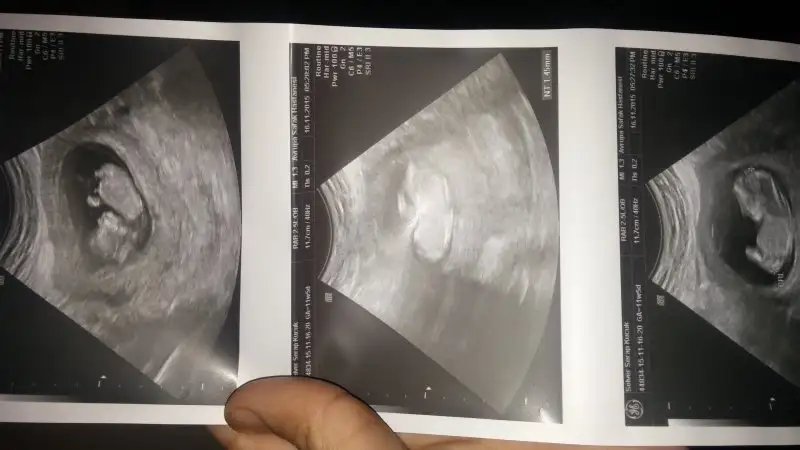

Erkek canim soldadir bebisin :)Kizlar benimkini yorumlar misiniz lutfeeeeeen :) karindan görüntü![]()

7+3 de karından canim ilk olan usg 5 haftalık olan vajinal insallah dedigin gibidir canim yaamrb canım ben ilk önce ulrason görüntülerini büyük sandım. o yüzden plasenta yönü yorumu yapmadım ama ikinci foto 7+3 günlükmüş. orda plasenta sağ altta görünüyor şayet ultrason karındansa kız, vajinal ise erkek olma ihtimali yüksek canım. allah gönlüne göre versin canım.

Arkadaşlar hep erkek demiş ama ben plasentayı sağ altta gibi gördüm canım. Karından ultrason da sağ altta ise kız deniyor. Senin gönlün hangi cinsiyetten yana ise o olur inşallah :)7+3 de karından canim ilk olan usg 5 haftalık olan vajinal insallah dedigin gibidir canim yaa